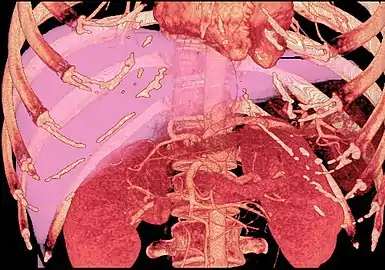

Technique

Before transplantation, liver-support therapy might be indicated (bridging-to-transplantation). Artificial liver support like liver dialysis or bioartificial liver support concepts are currently under preclinical and clinical evaluation. Virtually all liver transplants are done in an orthotopic fashion; that is, the native liver is removed and the new liver is placed in the same anatomic location.[7] The transplant operation can be conceptualized as consisting of the hepatectomy (liver removal) phase, the anhepatic (no liver) phase, and the postimplantation phase. The operation is done through a large incision in the upper abdomen. The hepatectomy involves division of all ligamentous attachments to the liver, as well as the common bile duct, hepatic artery, hepatic vein and portal vein. Usually, the retrohepatic portion of the inferior vena cava is removed along with the liver, although an alternative technique preserves the recipient's vena cava ("piggyback" technique).

The donor's blood in the liver will be replaced by an ice-cold organ storage solution, such as UW (Viaspan) or HTK, until the allograft liver is implanted. Implantation involves anastomoses (connections) of the inferior vena cava, portal vein, and hepatic artery. After blood flow is restored to the new liver, the biliary (bile duct) anastomosis is constructed, either to the recipient's own bile duct or to the small intestine. The surgery usually takes between five and six hours, but may be longer or shorter due to the difficulty of the operation and the experience of the surgeon.

The large majority of liver transplants use the entire liver from a non-living donor for the transplant, particularly for adult recipients. A major advance in pediatric liver transplantation was the development of reduced size liver transplantation, in which a portion of an adult liver is used for an infant or small child. Further developments in this area included split liver transplantation, in which one liver is used for transplants for two recipients, and living donor liver transplantation, in which a portion of a healthy person's liver is removed and used as the allograft. Living donor liver transplantation for pediatric recipients involves removal of approximately 20% of the liver (Couinaud segments 2 and 3).